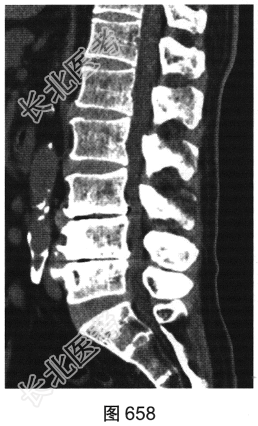

- 多项选择题2.[提示]患者行腰椎X线及CT检查,见图655~图659。患者有哪些阳性影像学表现( )

A、椎间盘“真空现象”

B、腰椎前滑脱

C、椎间盘膨出、突出

D、腰椎轻度侧弯

E、椎小关节骨质增生硬化

F、腰椎间隙变窄